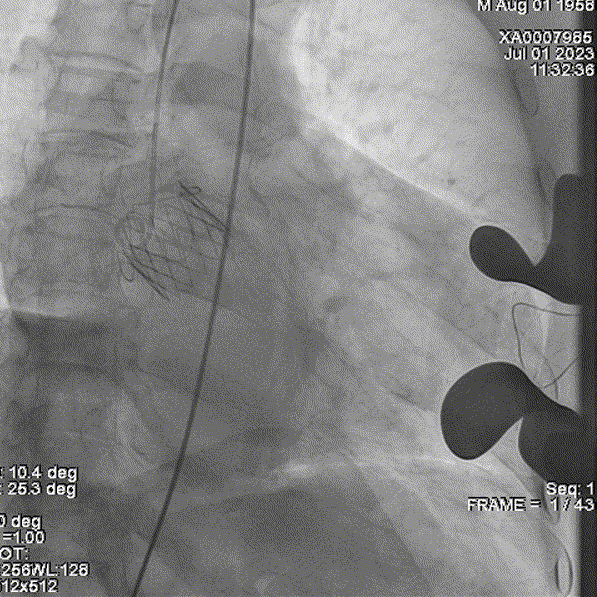

复查根部造影,未见明显反流,瓣膜形态和位置满意,双侧冠脉显影良好:

即刻复查超声,瓣架位置合适、形态佳,瓣叶功能正常,未见明显反流: